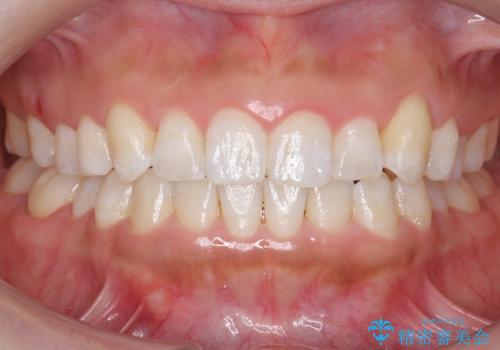

![[ 受け口傾向のマウスピース矯正 ] マイクロインプラントで行う確実な後方移動の症例 治療前](https://seimitsushinbi.jp/wp/wp-content/uploads/2024/04/5f0bc38a5dfbfee2c682d1aed8343d4d-500x350.jpg?v=1712301054)

![[ 受け口傾向のマウスピース矯正 ] マイクロインプラントで行う確実な後方移動の症例 治療後](https://seimitsushinbi.jp/wp/wp-content/uploads/2024/04/2095617952f97867f275f6769d72e82a-500x350.jpg?v=1712301056)

[ 受け口傾向のマウスピース矯正 ] マイクロインプラントで行う確実な後方移動